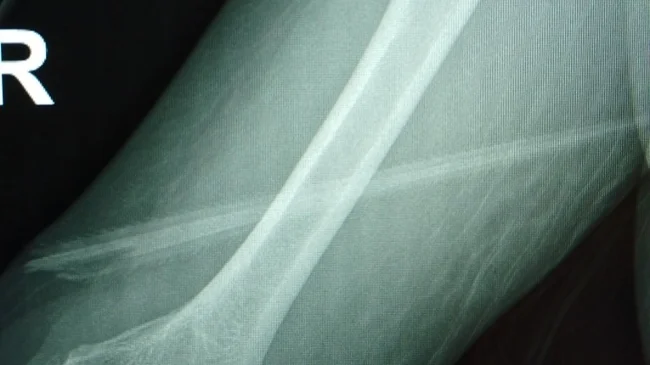

На рентгеновских снимках было видно, что шип пронзил руку женщины, как кинжал: вошел чуть выше правого локтя и вышел почти из-под мышки, едва не задев артерию. «Оглядываясь назад, я чувствую себя так, будто выиграла в лотерею», — призналась женщина.